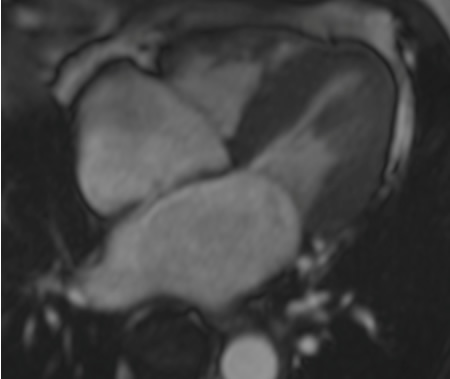

[Figure caption and citation for the preceding image starts]: Ressonância nuclear magnética cardíaca (RNMC) exibindo cardiomiopatia restritiva com dilatação biatrial e hipertrofia ventricular esquerda concêntrica leveDo acervo de Dr Jessica Webb; usado com permissão [Citation ends].

[Figure caption and citation for the preceding image starts]: Ressonância nuclear magnética cardíaca (RNMC) confirmando aumento do átrio esquerdo e hipertrofia ventricular esquerda (HVE)Do acervo de Dr Jessica Webb; usado com permissão [Citation ends].